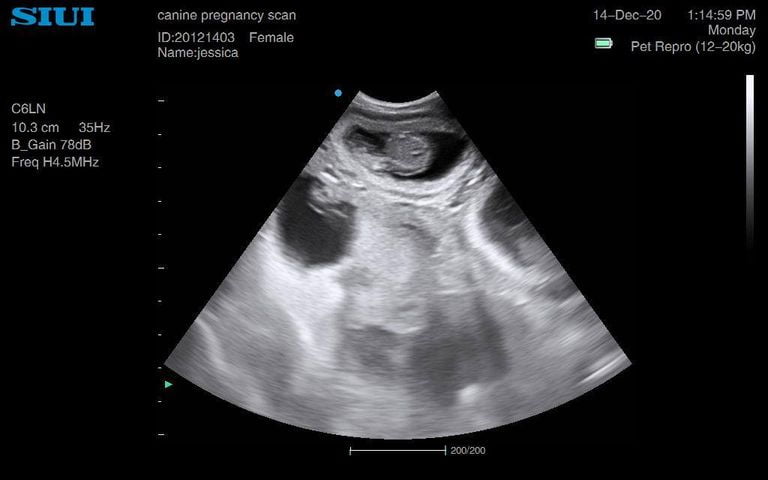

Jack Russell 6 weeks

Jack Russell already looking very rounded, head measurements at 5 weeks 6 days. She had four last litter, and we saw a minimum of four on this scan. Owners said